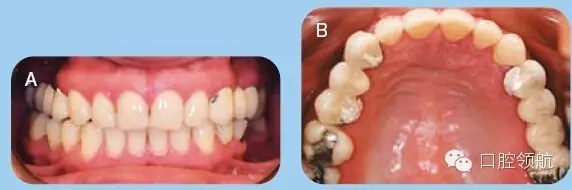

35歲白人女性患者,前來牙周科咨詢,要求修復(fù)兩側(cè)上頜象限的無牙頜區(qū)域。已存的固定橋修復(fù)失敗,患者要求行種植修復(fù)缺失牙。拆除患者已存的固定橋,重新預(yù)備基牙,并粘結(jié)臨時橋(圖1)。

圖1 (A)上頜以及下頜牙咬合關(guān)系的口內(nèi)照。(B)上頜牙弓的牙合面觀。

● 兩側(cè)上頜1/4象限的缺牙區(qū)牙槽嵴在頰舌向以及垂直向形態(tài)欠佳(Seibert III類)(圖1)。